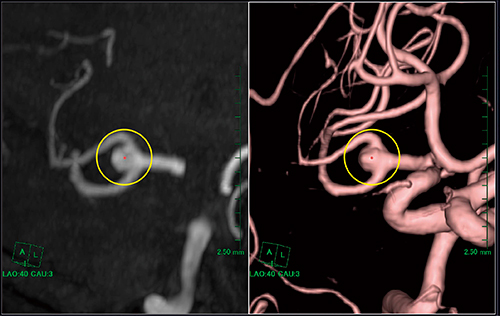

(5)VRまたはMIPで動脈瘤の長短軸が見やすいアングルに合わせ,長軸および短軸径を計測する(図6)。

図6 長短軸径の計測

AZE VirtualPlace 新NTのSliding MIPビューアを用いることにより,閾値の違いによる誤差を最小限にとどめ,VRと同様の角度からの動脈瘤の長軸および短軸径を簡単に計測することができた。